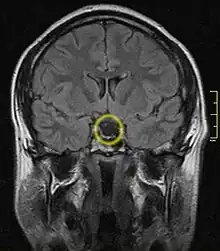

Empty sella turcica on MRI as seen in severe cases of Sheehan's syndrome | |

MRI is useful in diagnosing Sheehan's syndrome since it examines the structure of the pituitary and may identify any anatomical damage.[4] MRI findings will vary based on how early or late in the disease process the test is being conducted. If an MRI is conducted early enough in the disease process the pituitary may appear larger than normal, and show changes that are consistent with damage from lack of blood supply.[15] Later in the disease process of this syndrome the damage imposed on the pituitary gland will cause it to shrink, and leave a partially empty or totally empty sella turcica on MRI.[7]